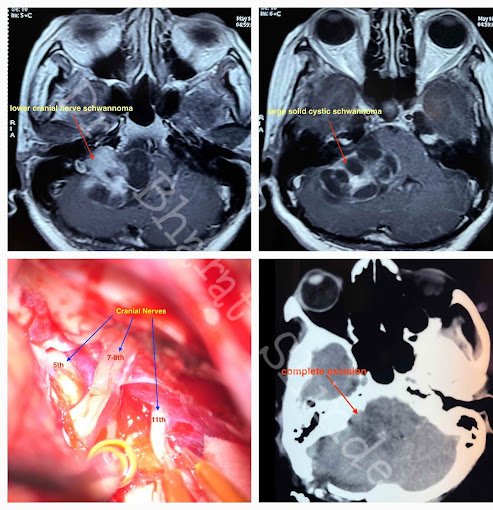

Which nerves are called as Lower cranial nerves:

What is Schwannoma ?

Nerves are covered with Schwann cells. Tumor arising from it is called as Schwannoma.

What are the clinical features of Schwannoma ?

Schwannoma arising from any nerve impair function of that nerve. As lower cranial nerves helps in swallowing movements ,patients having lower cranial nerve schwannoma present with swallowing difficulty , nasal regurgitation, cough while drinking water.As tumor size increases it compresses brainstem, cerebellum leading patient to have swaying while walking , difficulty in balancing .

Are these tumors treatable ?

Smaller tumors less than 3 cm can be treated with GKRS , a form of radiotherapy. It controls growth rate of tumor. It requires close follow up and regular interval MRI of patient to see Increase in size.

Larger tumor requires surgery where part of bone behind ear is removed and tumor is decompressed with microscope.

Lower Cranial nerves entering jugular fossa

Facial -Vestibulocochlear nerve complex entering IAM

Spinal Accessory Nerve